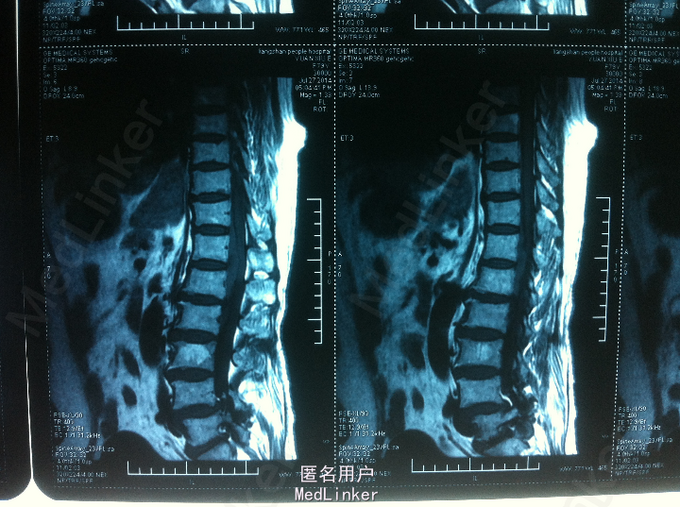

双下肢麻木、无力1天 患者老年女性,既往高血病史; 患者1天前无明显诱因起身时出现双下肢麻木,并加重,15分钟后出现双下肢无力,活动受,不能自行行走,无颈部疼痛及双上肢放射性疼痛、麻木、无力,无发热,寒战。

查体:腰部叩痛,双下肢感觉减退,双下肢肌力2-3级,双侧膝跟腱反射未引出,肌张力减弱,巴氏征未引出。 CT:腰椎硬膜外血肿可考虑 MR:腰椎硬膜外血肿

诊断:自发性腰椎硬膜外血肿 患者入院后给予甘露醇、甲泼尼龙、甲钴胺、神经节苷脂等药物,第二天,双下肢麻木较前减轻,双下肢肌力3-4级,与患者及家属沟通后,患者家属拒绝手术减压血肿清除,继续给予消肿、营养神经药物治疗,入院第5天,患者双下肢麻木明显消失,双下肢肌力4-5级,好转出院。